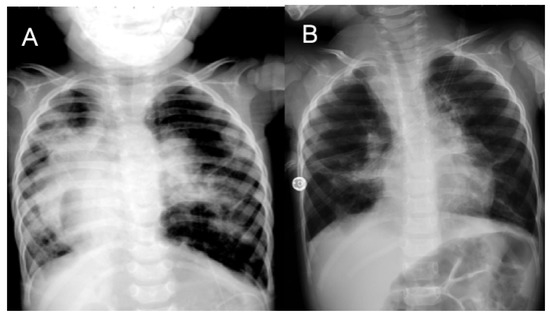

3.2. Case 2

3.3. Case 3